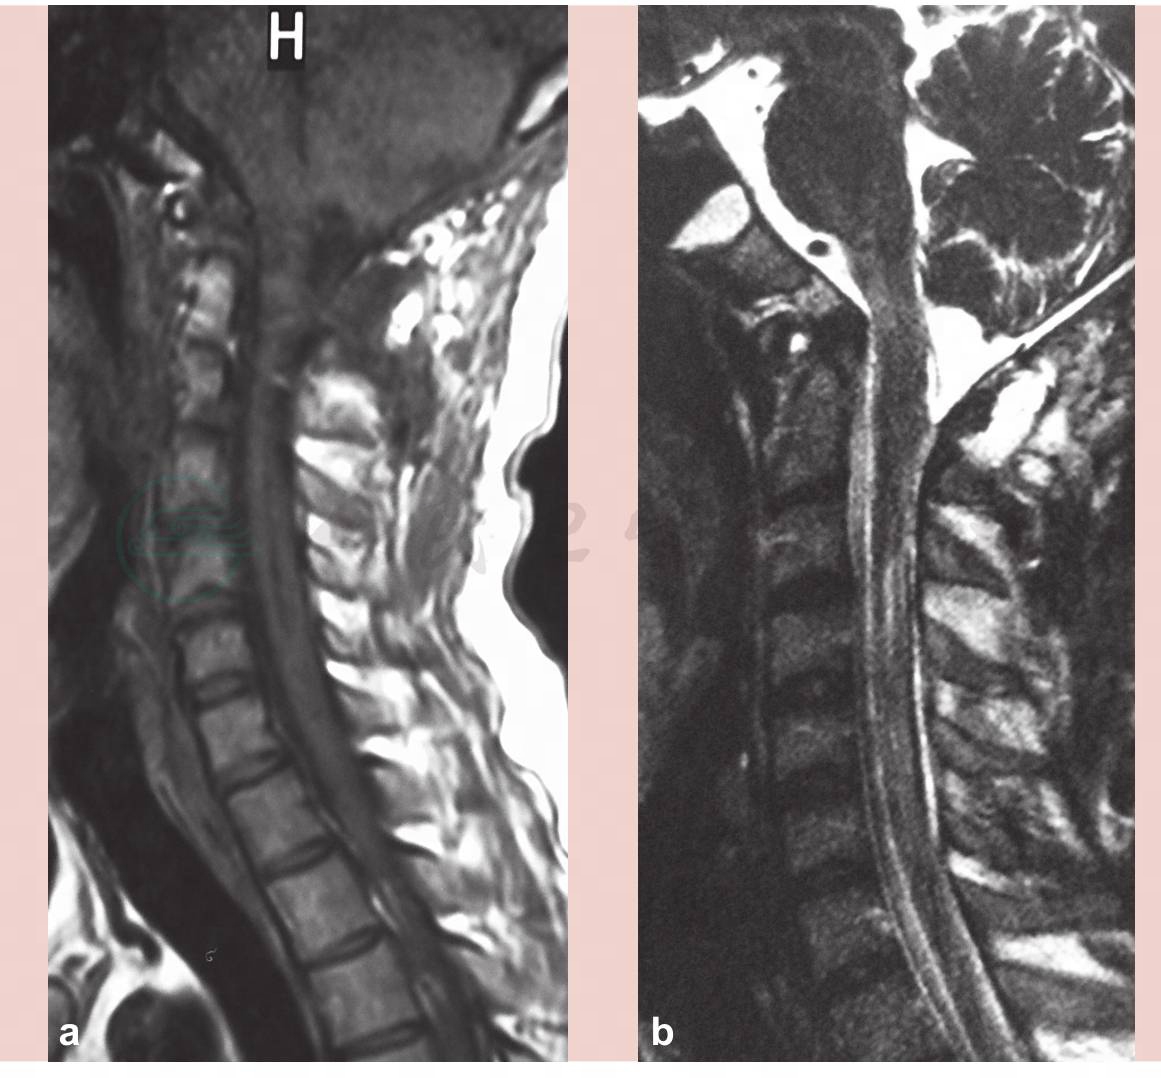

图1 第一次术前磁共振(MRI)示小脑扁桃体下疝合并脊髓空洞

a.T1像;b.T2像